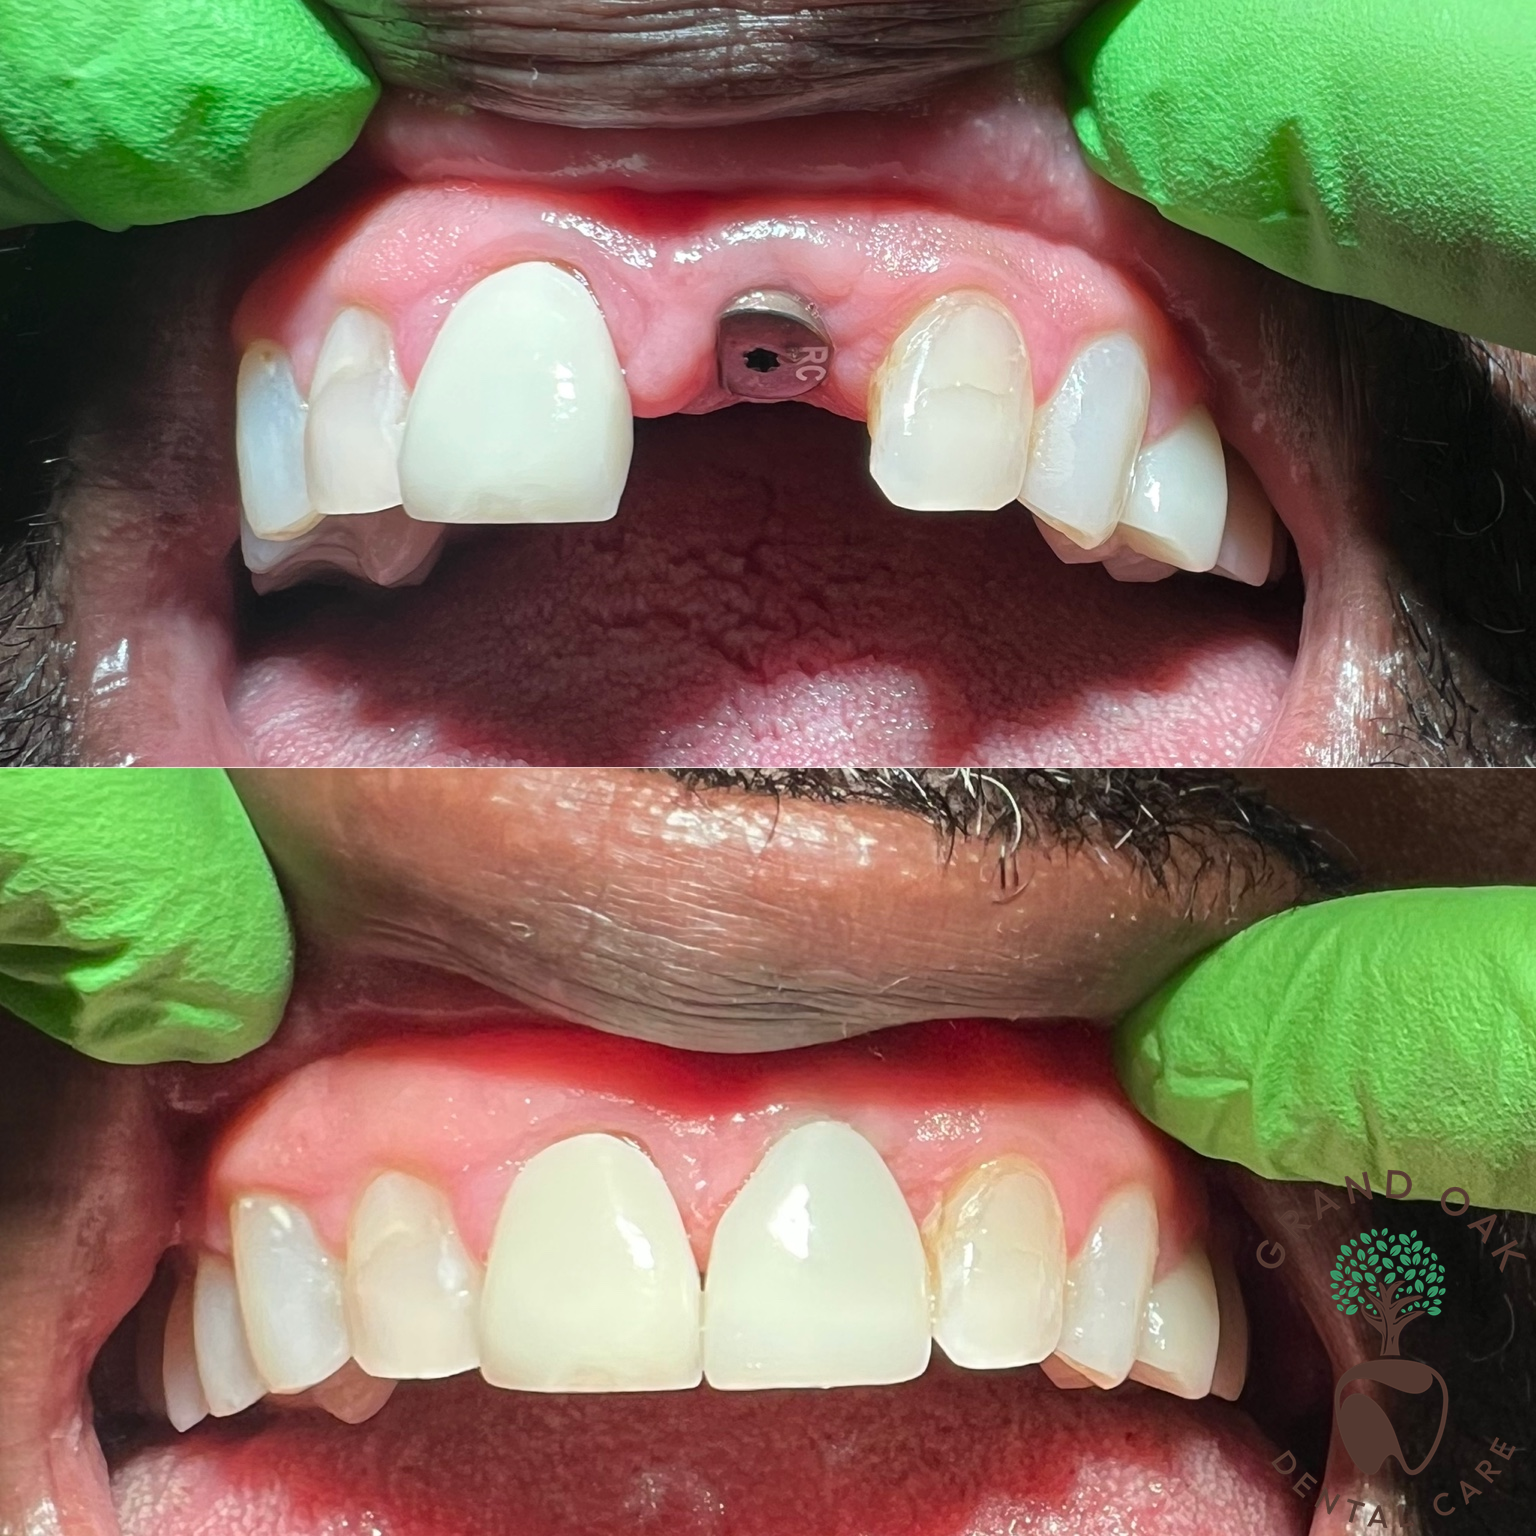

Anterior Implant Single Tooth

✨ Front tooth implant restoration at Grand Oak Dental Care in Antioch! ✨ This patient came to us missing a front tooth and wanted a natural-looking, long-term solution. Our dentist placed a dental implant to replace the missing tooth, and once healing was complete, we removed the healing abutment and took a precise digital impression. Using advanced digital dentistry, we fabricated a custom abutment and bonded a translucent, esthetic zirconia implant crown to perfectly match the surrounding teeth. The result is a strong, natural-looking restoration that blends seamlessly with the smile and restores confidence. If you're missing a front tooth and want a permanent, beautiful solution, our dentist in Antioch can help. Contact Grand Oak Dental Care today to schedule your consultation!